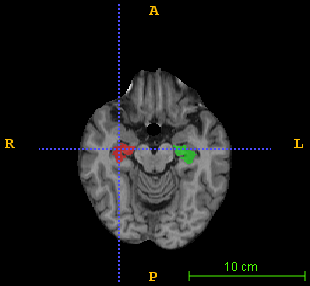

A validation study has been conducted on the brain MRI data drawn from the Alzheimer’s Disease Neuroimaging Initiative database (http://adni.loni.usc.edu). As a pilot study, 100 brain images were randomly picked: 34 healthy subjects, 33 with mild cognitive impairment (MCI) and 33 AD patients, with a demographic profile presenting no statistically significant difference on age and MMSE score from the whole database (pβˆ’v​a​l​u​e>0.1π‘π‘£π‘Žπ‘™π‘’π‘’0.1p-value>0.1). All images were bias-corrected and linearly aligned in the widely-used MNI152 template space. Each image also includes a reference manual segmentation of the hippocampus. A sample image superimposed with its label map is shown in Fig. 1.

Figure 1: A sample brain MR image superimposed with its hippocampus reference segmentation in (left) axial view, (middle) sagittal view, and (right) coronal view. The green and pink colored regions respectively indicate the left and right hippocampus